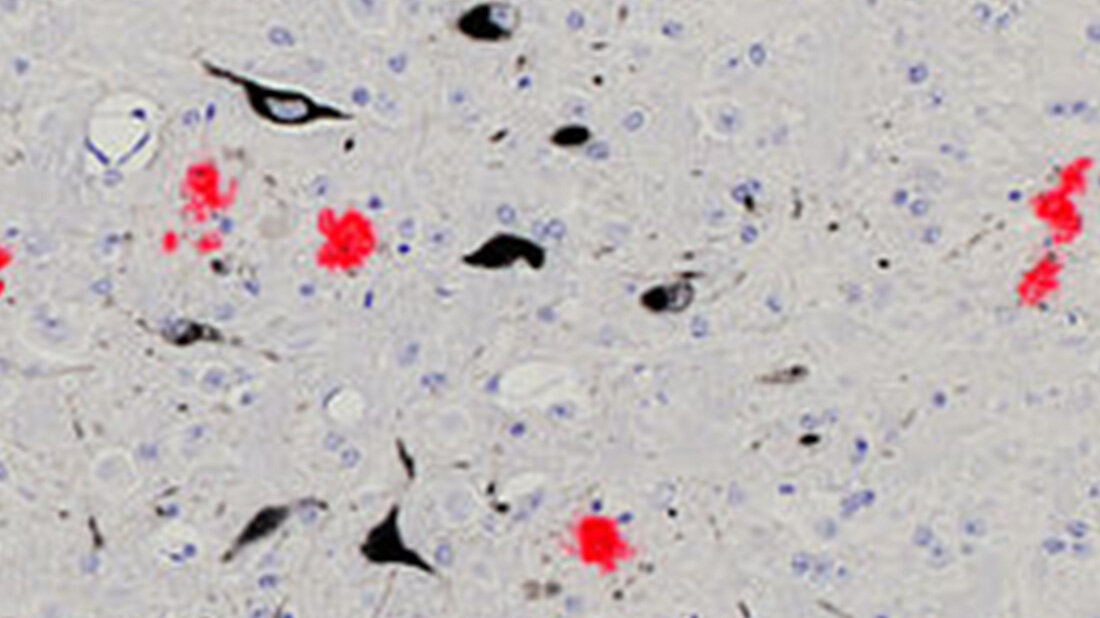

Hauptursache für die Entstehung der Alzheimerkrankheit scheint die Ablagerung eines bestimmen Eiweißes, des Beta-Amyloid-Proteins, im Gehirn zu sein – so der aktuelle Stand der Alzheimerforschung. Die Bildung dieser sogenannten Plaques beginnt mindestens zwanzig Jahre vor den ersten Krankheitssymptomen. Bislang fand man bei Erkrankten jedoch nur einen schwachen Zusammenhang zwischen der Menge der Ablagerungen und den klinischen Symptomen. Grund dafür könnte sein, dass sich die Krankheit in fortschreitenden Stadien unabhängig von den Plaques weiterentwickelt. Das legt eine aktuelle Studie von Forschenden um Prof. Dr. Mathias Jucker vom Hertie-Institut für klinische Hirnforschung, der Universität Tübingen und dem Deutschen Zentrum für Neurodegenerative Erkrankungen (DZNE) nahe. Eine Therapie müsse daher so frühzeitig wie möglich begonnen werden, so Jucker. Die Ergebnisse sind in der aktuellen Ausgabe der renommierten Zeitschrift „Nature Communications“ erschienen.

Das Tübinger Forschungsteam liefert nun erstmals experimentelle Belege für die Entkopplung der Ablagerungen von der nachgeschalteten Neurodegeneration. In ihrer Studie untersuchte es Mäuse, die als Alzheimermodell dienen. Bei ihnen lagern sich – wie bei Alzheimererkrankten – mit fortschreitendem Lebensalter Beta-Amyloid-Eiweiße im Gehirn ab. Die Wissenschaftlerinnen und Wissenschaftler reduzierten nun bei den Mäusen in unterschiedlichen Altersstadien gezielt die Plaques. Dann maßen sie ein weiteres Protein im Hirnwasser der Mäuse, das sogenannte Neurofilament-Leichtketten-Protein (NfL). Das NfL-Protein ist im Hirnwasser von Alzheimererkrankten erhöht; es gilt als Anzeiger für den Abbau von Nervenzellen. Das Ergebnis: „Wenn wir die Beta-Amyloid-Ablagerung in frühen Stadien reduzierten, stieg die Menge an NfL-Protein im Hirnwasser nicht mehr an. Wir konnten den Abbau der Nervenzellen stoppen“, so Christine Rother, Erstautorin der Studie. Ein anderes Bild ergab sich im höheren Lebensalter: „Wenn wir die Bildung der Beta-Amyloid-Plaques in späteren Stadien reduzierten, stieg der Pegel des NfL-Proteins im Hirnwasser unverändert an. Es starben also weiterhin Nervenzellen. Die Neurodegeneration hatte sich von den Ablagerungen entkoppelt“, ergänzt Ruth Uhlmann, Co-Erstautorin der Arbeit. „Es scheint bei Alzheimer also zwei Phasen der Krankheitsentwicklung zu geben“, schlussfolgert Jucker. In der ersten Phase trieben die Beta-Amyloid-Plaques die Krankheit voran. Zu diesem Zeitpunkt seien Therapien, die den Ablagerungen entgegenwirken, höchst effektiv. In der zweiten Phase schreite hingegen die Neurodegeneration unabhängig von den Plaques fort. Gegen die Beta-Amyloid-Plaques gerichtete Therapien verfehlen nun weitgehend ihre Wirkung.